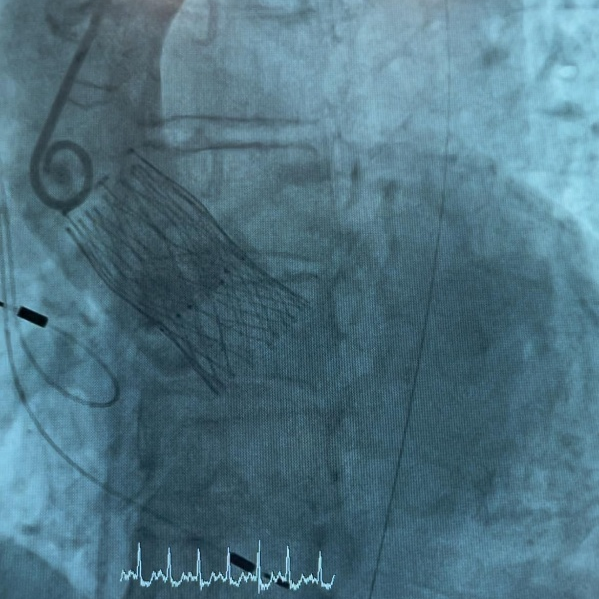

在IMPERIA?输送系统获批后联合ALLEGRA?于西班牙、德国完成全球首植后不久,意大利也传来喜讯,于那不勒斯Pineta Grande医院成功实现IMPERIA?输送系统与ALLEGRA?的联合植入。该植入针对一位高龄女性患者,由Arturo Giordano博士、Nicola Corcione博士、Michele Albanese博士和Alberto Morello博士团队完成,蓝帆柏盛国际团队现场支持。

该患者是一名83岁的女性,植入后获得卓越的临床结果:术前平均跨瓣压差:40 mmHg;术后平均跨瓣压差:8 mmHg;术后无瓣周漏发生。

放置后